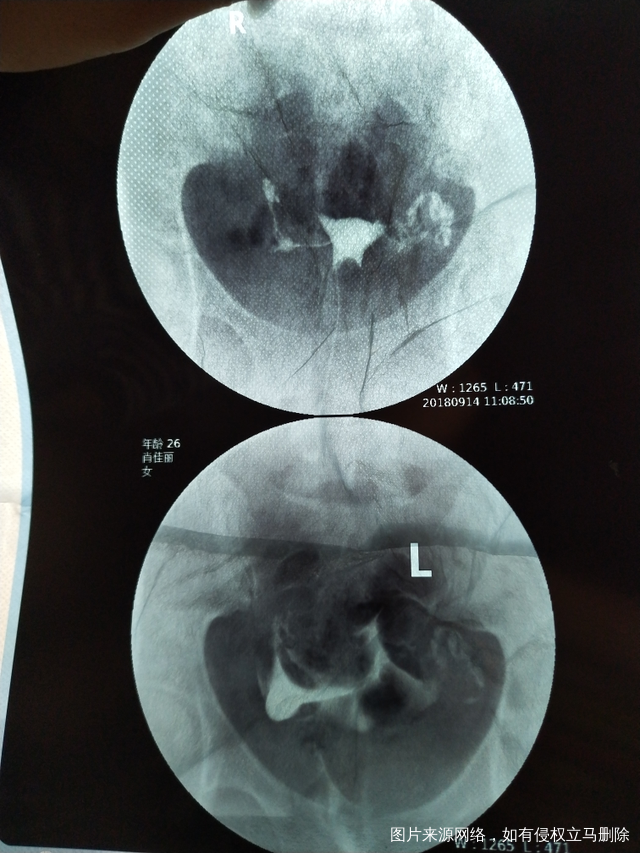

今天做了造影 医生帮我看下怎么样吧?